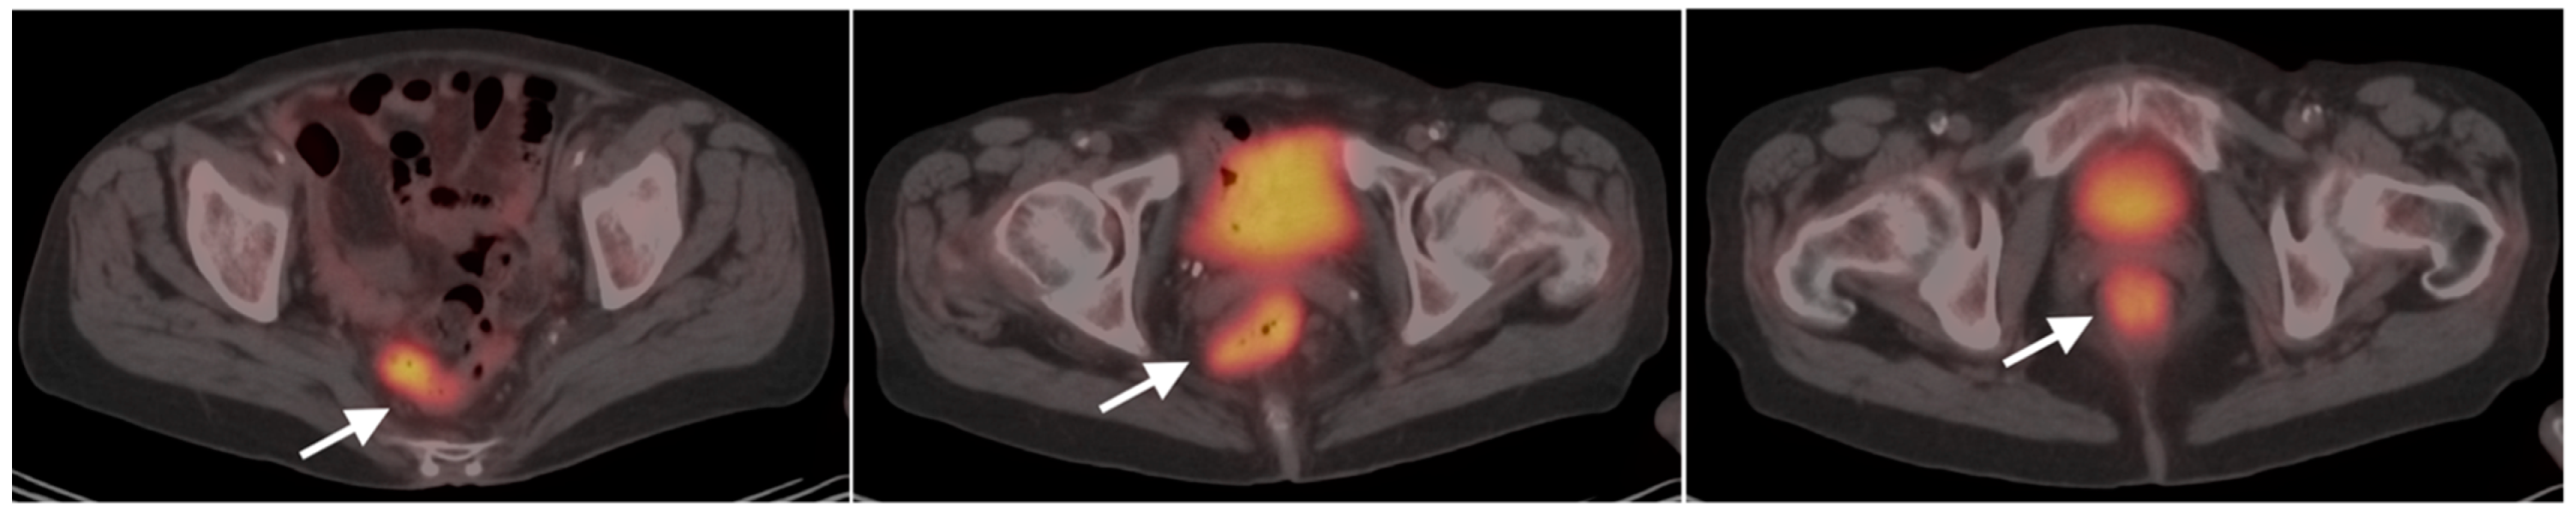

10. Anal Carcinoma